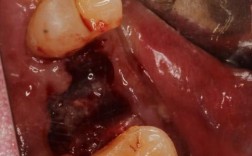

- 切开牙龈: 医生会在种植体顶部的牙龈上做一个小的切口,通常是小圆形或椭圆形切口。

- 分离牙龈: 轻轻分离牙龈组织,暴露埋在下面的种植体顶部。

- 连接基台: 使用专用工具,将选定的基台精确地拧入或连接到种植体的内部接口上,医生会确保基台的位置、角度高度合适。

- 塑形牙龈: 医生会仔细修剪牙龈组织,使其紧密、美观地贴合在基台周围,形成一个健康的牙龈袖口,有时可能需要做小的牙龈成形术。

- 缝合: 用可吸收缝线(有时也需要非吸收线)将牙龈切口缝合固定,有时医生也会选择不缝合,让伤口自然愈合(称为“开放愈合”或“愈合帽暴露”)。